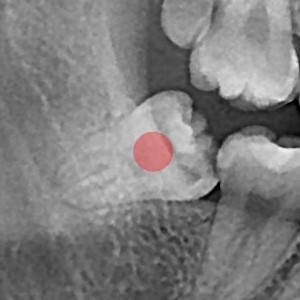

사랑니발치 10대/여성

5e20e086184bc11a2d853605b7813944_1764319875_366.jpg